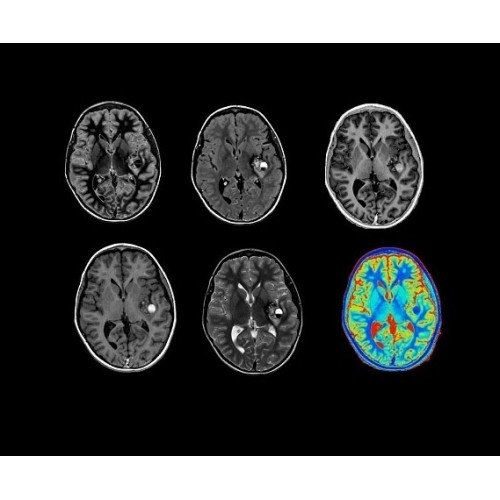

SIGNA PET/MR 3.0T — это гибридная система, в которой совмещаются две принципиально разные технологии — магнитно-резонансную томографию (МРТ) и позитронно-эмиссионную томографию (ПЭТ). Система отличающийся высокой чувствительностью и эффективностью и предназначена для диагностики в области онкологии, неврологии, кардио-васкулярных исследований, исследований воспалительных процессов.

Компания GE Healthcare представляет революционную, полностью интегрированную систему SIGNA PET/MR1, в которой сочетаются времяпролетная технология (TOF) и возможности напряженности магнитного поля 3.0 Тл. Мы поможем вам поднять исследования на более высокий уровень. SIGNA PET/MR позволяет достичь впечатляющей точности и скорости исследований, а благодаря новейшей технологии реконструкции Q.Clear2 качество изображений улучшается в два раза. Кроме того, в систему включен полный набор клинических приложений и гибких катушек для проведения любых видов исследования, открывая для вас возможности визуализации, о которых вы даже не догадывались.

Кроме того, в результате использования технологии TOF и инновационной технологии реконструкции Q.Clear вы сможете добиться прекрасного соотношения сигнал/шум. А благодаря технологии нулевого времени эхо (ZTE) визуализировать костную структуру без ионизирующего излучения. Все эти разработки для улучшения качества сканирования и точности анализа помогут вам использовать весь потенциал ПЭТ/МРТ.

• Q.Clear — в основу технологии легли накопленные знания о том, как минимизировать помехи при реконструкции и получить четкое изображение. При значительном улучшении качества изображения сохраняется точность расчетов. Сочетание технологии TOF и реконструкции Q.Clear — ваш надежный помощник для получения точных и достоверных данных.

• Специальный пакет приложений для измерения и сравнения объемных изображений ЦНС с нормами поможет вам в диагностике нейродегенеративных заболеваний, а дополнительные инструменты визуализации — в постановке точного диагноза с помощью бета-амилоидов и радиоизотопных маркеров ФДГ.